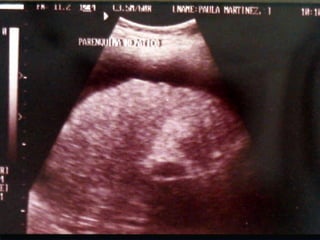

TOMOGRAFIA COMPUTADA DENSIDADES TOMOGRÁFICAS. Hiperdenso.( Sangre, litos de calcio). Isodenso. (Parénquima normal).  Hipodenso (líquido).

TOMOGRAFIA CONPUTADA HALLAZGOS: Patrón hiperdenso de tumoración  No  reforzamiento y patrón hipodenso en interior de tumoración, con nivel ( Absceso) Reforzamiento con medio de contraste:(neoplasias vascularizadas, pancreatitis hemorrágica) Reforzamiento exclusivo pared (Quiste) Patrón hipodenso difuso ( pancreatitis aguda, cirrosis o neoplasia hepática

TOMOGRAFIA COMPUTADA HALLAZGOS:   Visualizar vísceras sólidas (hígado, páncreas, riñón y bazo) Visualizar con medio de contraste ( esófago, estómago, intestino delgado y grueso). Visualizar (estructuras vasculares y ganglios). Visualización  espacios (peritoneal y de morrison) y sus contenidos.